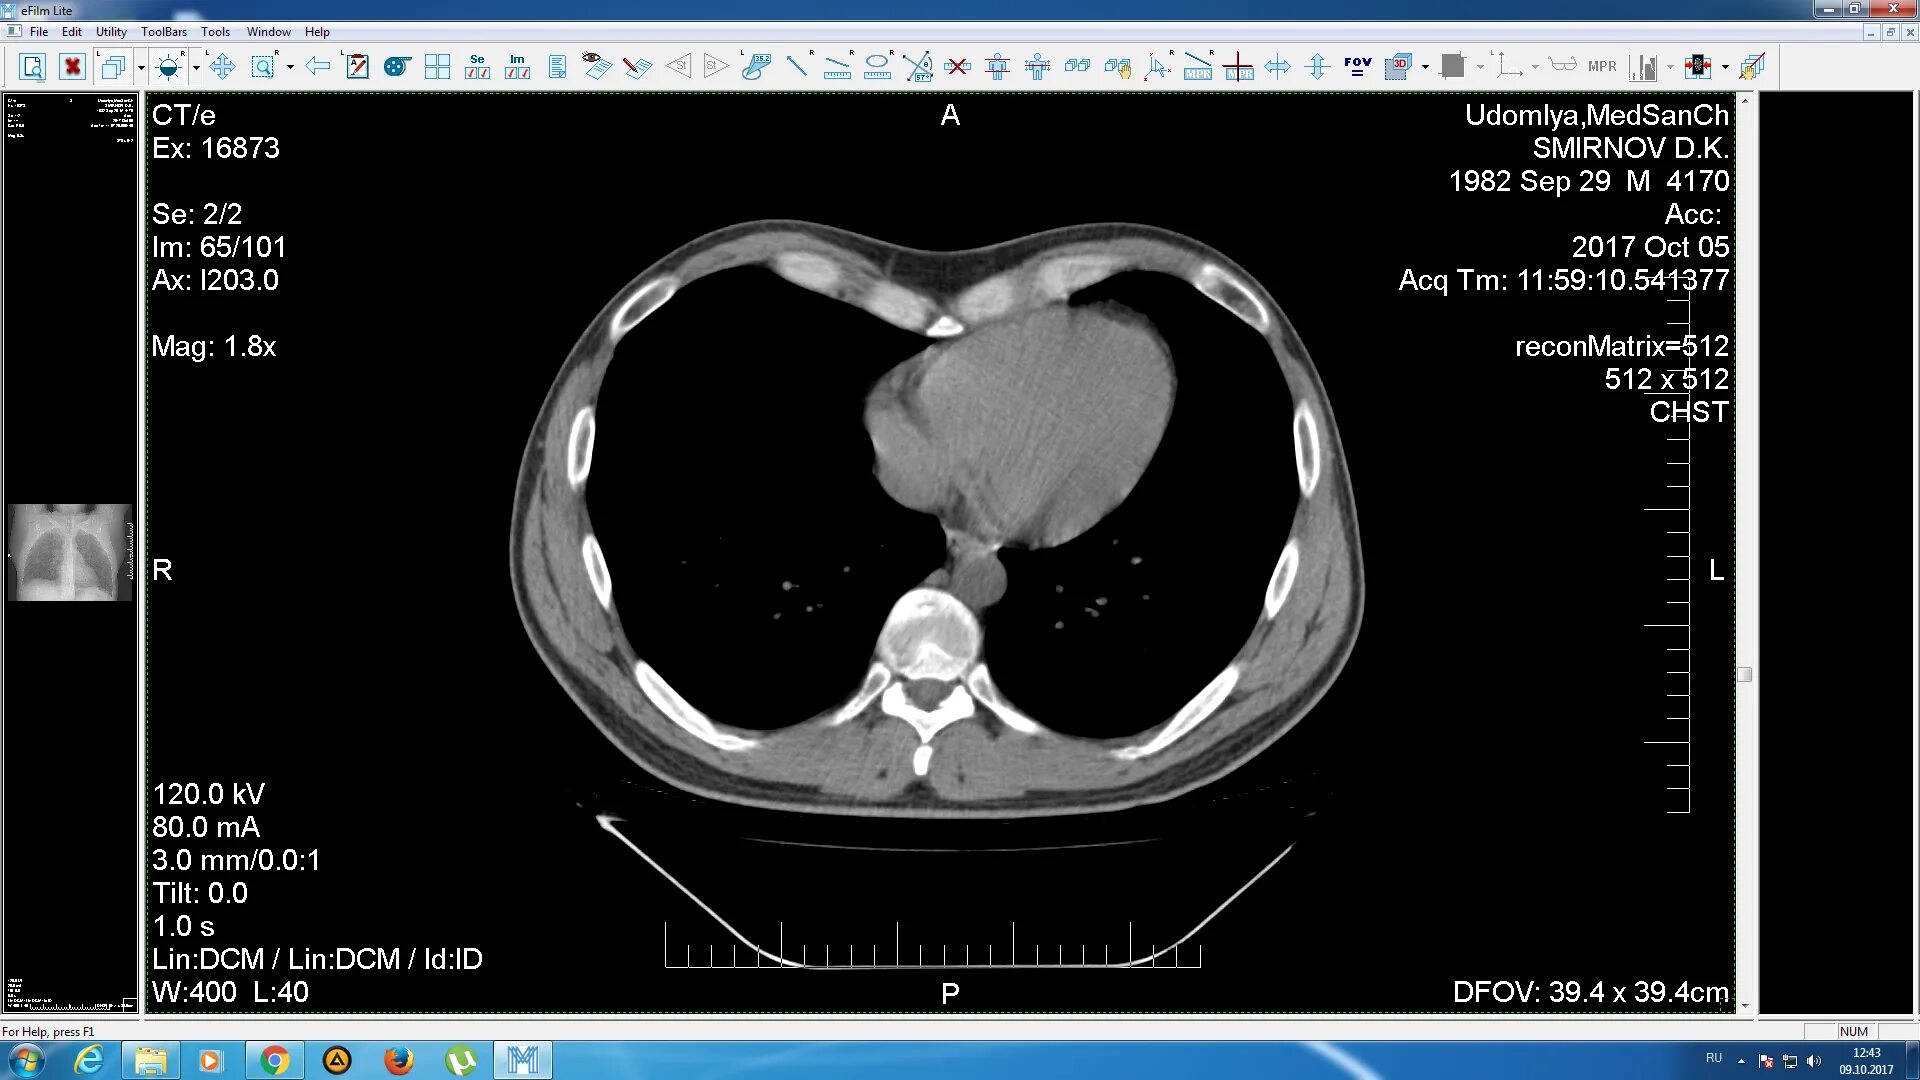

Данные кт